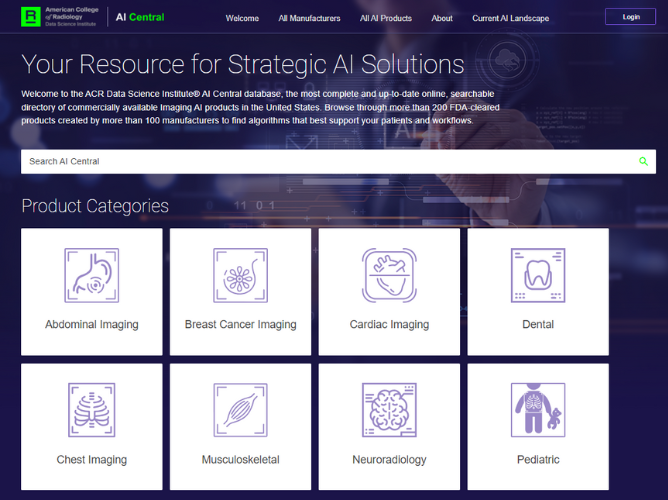

Transparency in #ImagingAI products is increasingly important. That's why @AcrDsi added two new programs to their imaging AI directory AICentral.org. Learn more about Transparent-AI and what this means for the future of imaging AI: bit.ly/3RsoUJw @RadiologyACR

.@waldchristoph ushers in a new era of transparency with AI-Central. 🙌 Read more on the Transparent-AI initiative and learn how you can identify the most optimal AI solutions to enhance your radiology practice 👉 bit.ly/42DsDrL #ImagingAI

The new AICentral.org simplifies finding imaging AI products by providing a centralized platform for searching and comparing products. Find out more 👉 bit.ly/4b1iw3C @AcrDsi #RadiologyAI #ImagingAI #radiology @RadiologyACR

.@waldchristoph ushers in a new era of transparency with AI-Central. 🙌 Read more on the Transparent-AI initiative and learn how you can identify the most optimal AI solutions to enhance your radiology practice 👉 bit.ly/42DsDrL #ImagingAI